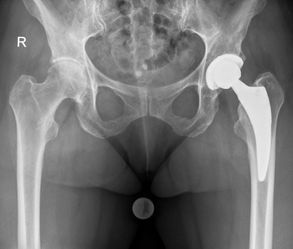

Prothetischer Gelenkersatz (minimalinvasiv) von Hüfte und Knie